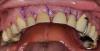

anvladd Опубликовано 24 июля, 2012 Поделиться Опубликовано 24 июля, 2012 (изменено) всем здравствуйте! какую временную конструкцию можно придумать в данном случае? Планируется удаление с одномоментной имплантацией(nobel) с отсроченной нагрузкой.http://s2.ipicture.ru/uploads/20120724/thumbs/Q1WHc6wr.jpg Изменено 24 июля, 2012 пользователем anvladd Ссылка на комментарий

Doc Опубликовано 25 июля, 2012 Поделиться Опубликовано 25 июля, 2012 Не самый лучший вариант. Во-первых, низкая клиническая коронка, каппа держаться толком не будет, кламмера тоже не за что цеплять. Во-вторых, по прикусу не пройдет, посмотрите, нижние зубы бьют в верхнюю десну. В-третьих, такие замечательные сосочки будут потеряны.А почему нагрузка отсроченная? Никак не сделать сразу? И что планируется вообще? Там для начала в любом случае нужно решать комплексно вопросы с прикусом. Ссылка на комментарий

anvladd Опубликовано 25 июля, 2012 Автор Поделиться Опубликовано 25 июля, 2012 Не самый лучший вариант. Во-первых, низкая клиническая коронка, каппа держаться толком не будет, кламмера тоже не за что цеплять. Во-вторых, по прикусу не пройдет, посмотрите, нижние зубы бьют в верхнюю десну. В-третьих, такие замечательные сосочки будут потеряны.А почему нагрузка отсроченная? Никак не сделать сразу? И что планируется вообще? Там для начала в любом случае нужно решать комплексно вопросы с прикусом.Хирург пока так решил что не стоит сразу нагружать,посмотрим после.Комплексно вопросы с прикусом пациент не хочет решать. Хочет один зуб и усе. Ссылка на комментарий